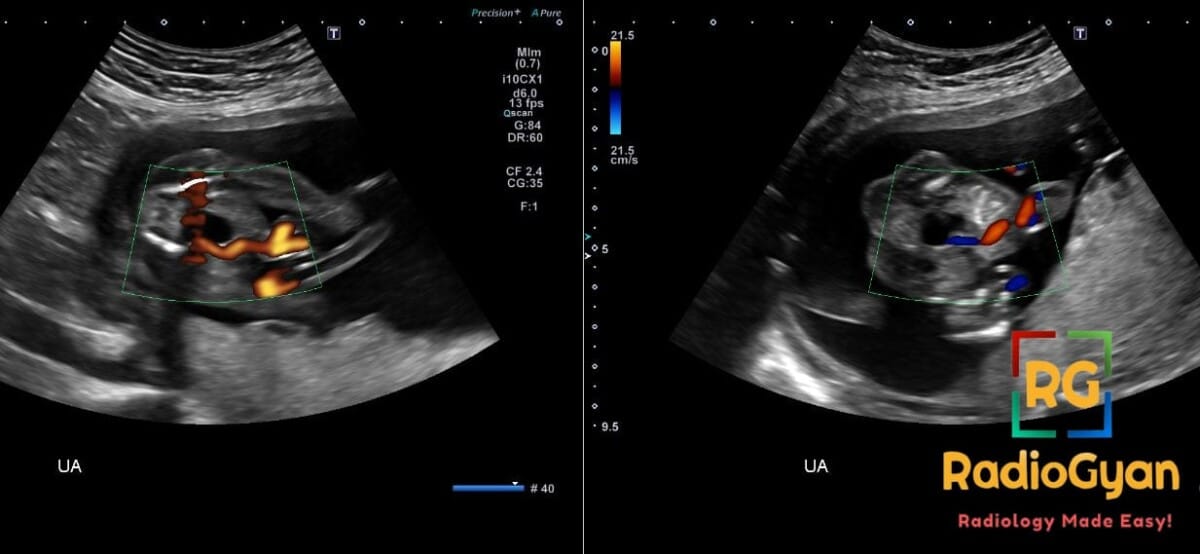

Routine second trimester screening ultrasound in a 28-year-old pregnant female.

Diagnosis: Single Umbilical Artery (SUA)

- US: Primary diagnostic tool; hallmark finding is visualization of only one artery coursing around the fetal bladder in cross-section; two-vessel cord appearance instead of normal three-vessel cord; 84% sensitive in the first trimester.

- Signs: Single Artery Around the Fetal Bladder sign (diagnostic hallmark); may see associated signs like increased nuchal translucency or hydronephrosis if non-isolated.